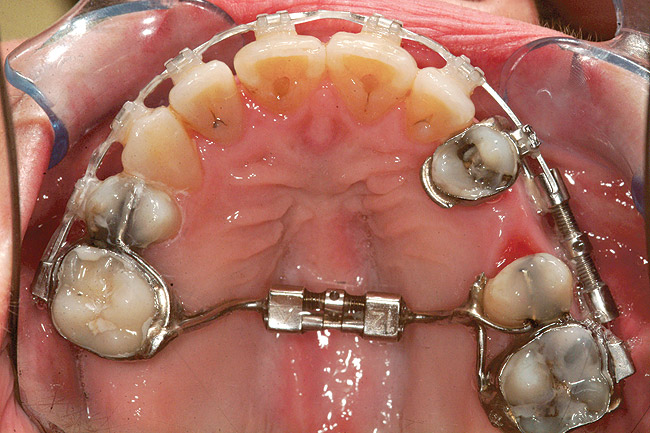

Fig 18 (through Fig 21). Note lack of alveolar development from congenitally missing Nos. 24 and 25. Surgical procedures after 5 months of orthodontic alignment included single-tooth osteotomies Nos. 6 to 11 and Nos. 21 to 28 and buccal corticotomies on all other teeth. Anchorage plate was stabilized to piriform rim.

Figure 18

Fig 20. Note lack of alveolar development from congenitally missing Nos. 24 and 25. Surgical procedures after 5 months of orthodontic alignment included single-tooth osteotomies Nos. 6 to 11 and Nos. 21 to 28 and buccal corticotomies on all other teeth. Anchorage plate was stabilized to piriform rim.

Figure 20

Fig 21 (and Fig 20). There is significant lateral dentoalveolar expansion of arches and alveoloskeletal correction in maxillary and mandibular anterior regions. Alveolar bone volume was increased in lower anterior to create optimal implant sites and establish ideal interincisal function and stability.

Figure 21